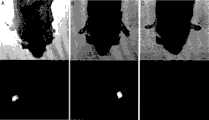

The target effect ofembodiment 3 fusion roteins in having transplanted the 129Sv mouse of subcutaneous F9 tumour

Target character in the body of the radioiodinated L19-IL10 preparation of bio distribution test evaluation that utilization is implemented in carrying the 129SvEv mouse of subcutaneous F9 teratocarcinoma.Intravenous administration is observed good tumour/organ ratio (scope at 7:1 between the 128:1) after 24 hours.The radioiodinated L19-IL15 of bio distribution test evaluation that utilization has been implemented in having carried the 129SvEv mouse of subcutaneous F9 teratocarcinoma, target character in the IL15-L19, the body of IL24-L19 and L19-GM-CSF preparation.Subcutaneous administration is observed good tumour after 24 hours: the organ ratio.